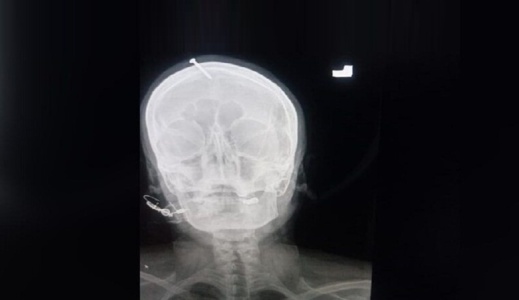

وأشار الدكتور إلى أن المرأة "كانت في كامل وعيها، لكنها كانت تعاني كثيرا". وكشفت صورة بالأشعة السينية بأن المسمار اخترق جمجمة الحامل لمسافة خمسة سنتيمترات لكنه لم يصل إلى الدماغ.